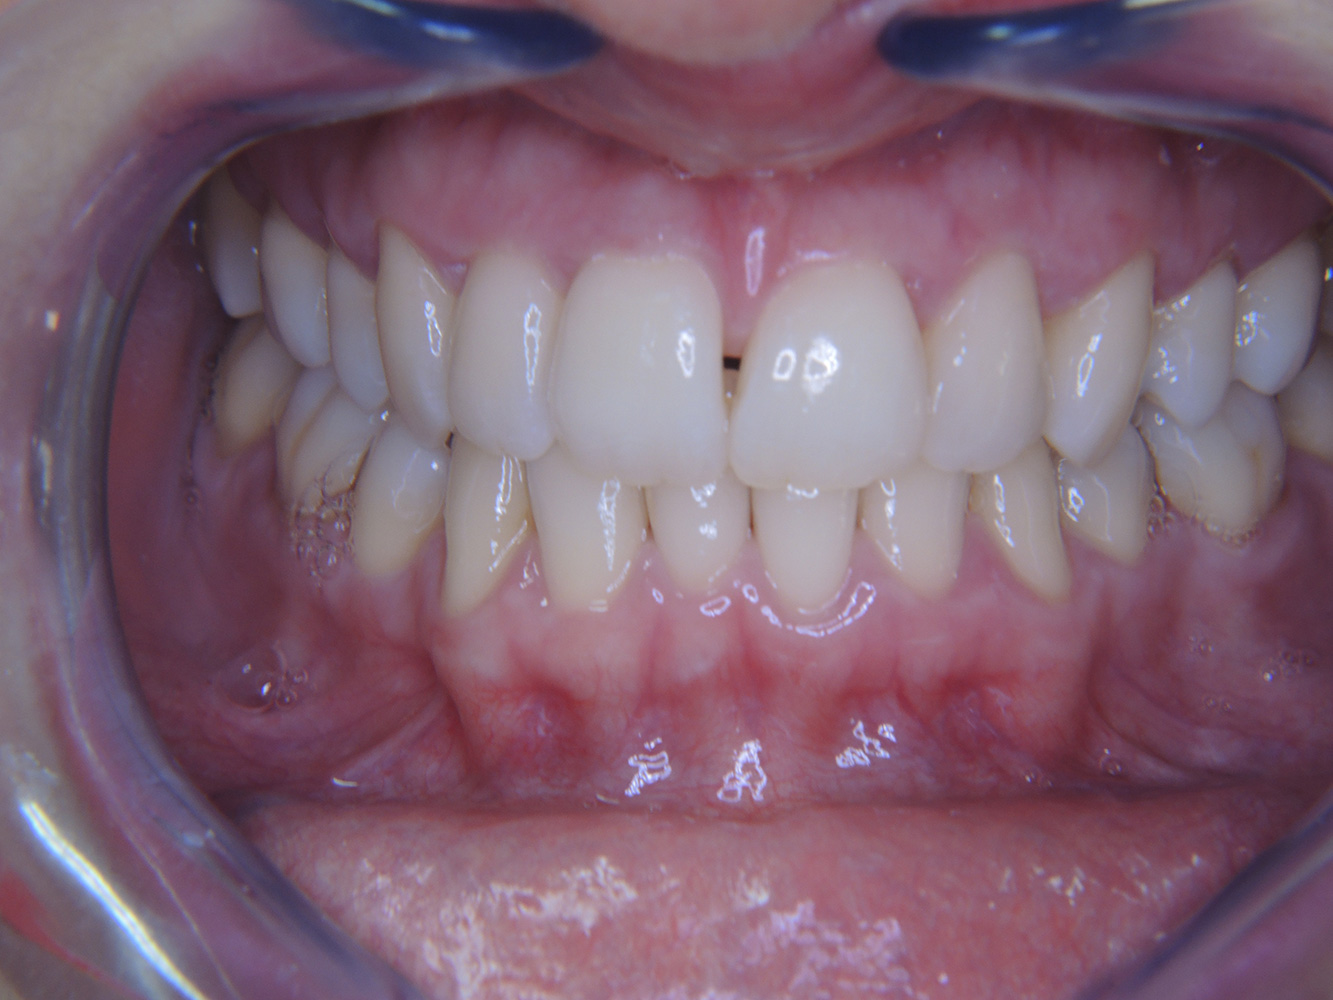

In the medical history, the 55-year-old patient states that he has no systemic disease and is not taking any medication. The patient’s lifestyle is similarly unremarkable. The patient has a few tooth restorations and two implants (2nd and 4th quadrants). On the basis of current findings, gingivitis is identified in an otherwise stable periodontal condition on the reduced periodontium (stage III, grade A). more

The healthy patient with pre-existing periodontal disease & peri-implantitis

The healthy patient with early periodontal disease